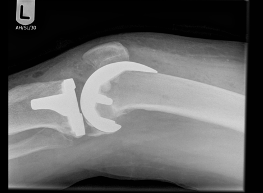

Images of Knee Replacement:

X-Ray of Knee Replacement 2